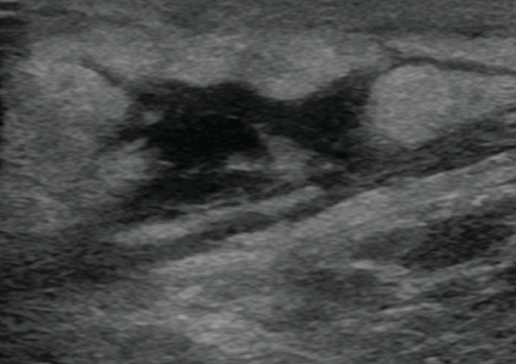

丹毒

皮下膿瘍